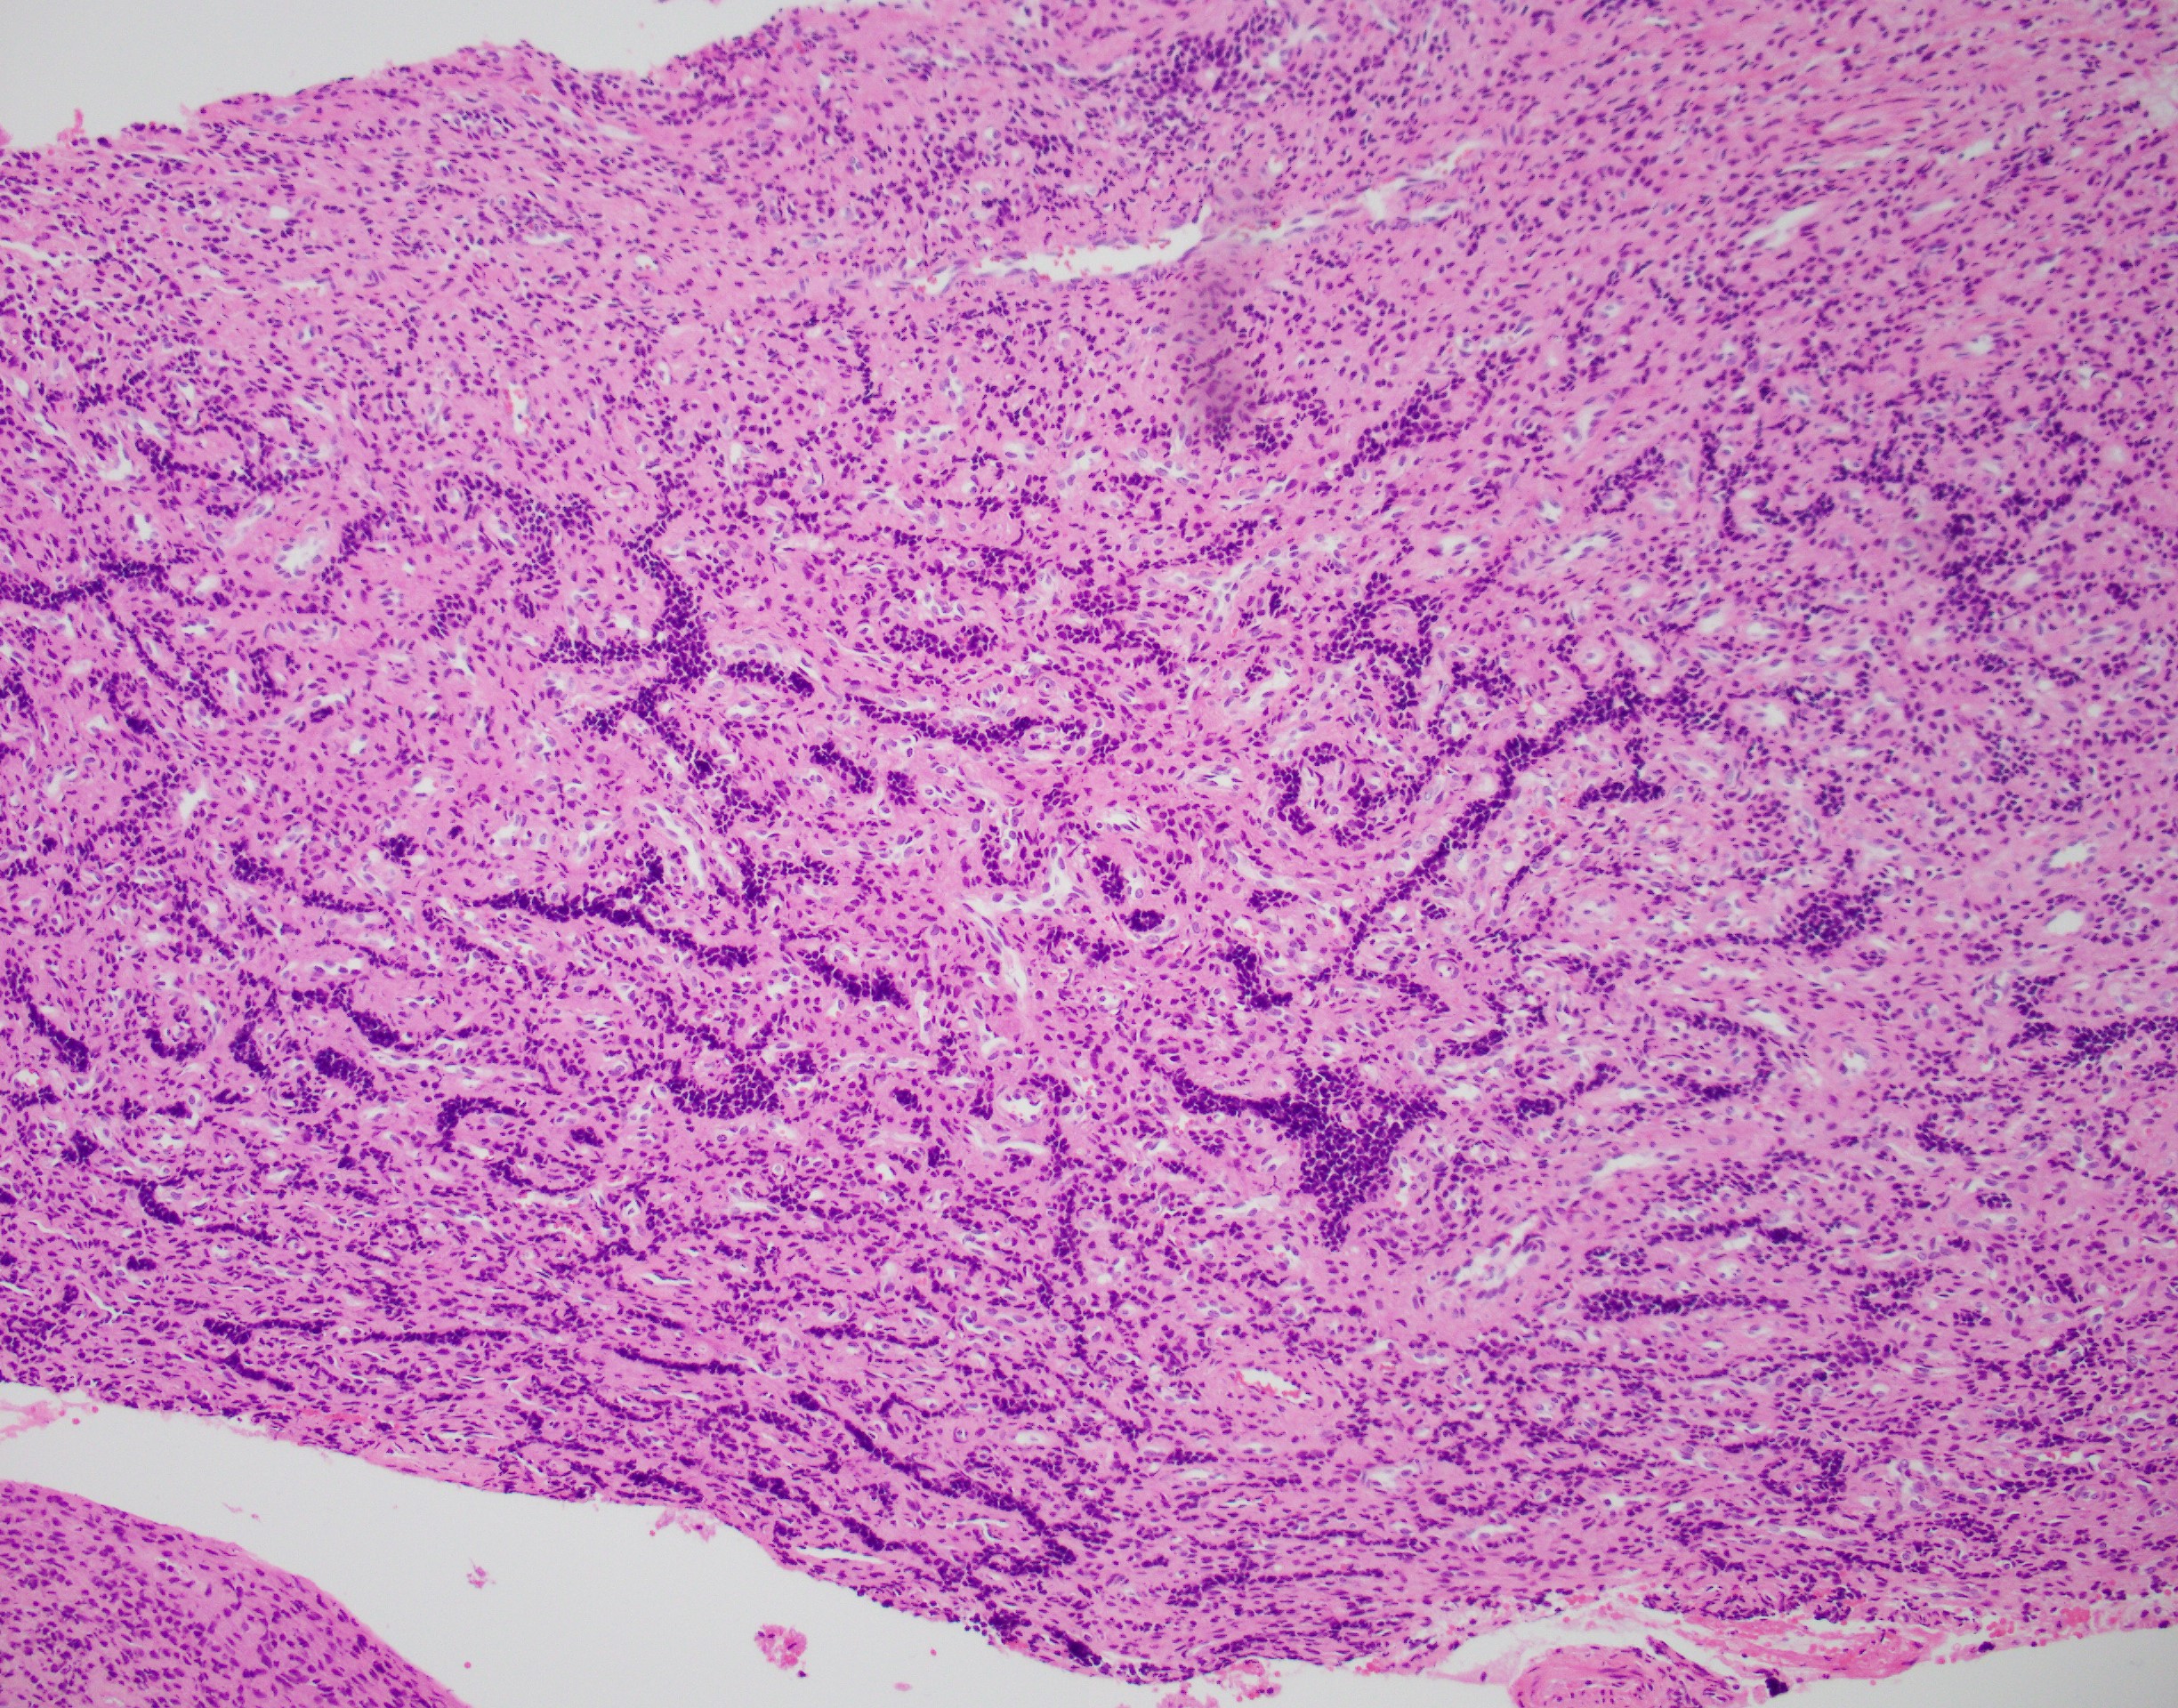

Sections show large polypoid, densely cellular fragments of endometrial stroma composed of bland cells that are small and uniform, resembling proliferative-type endometrial stroma. Admixed within this stroma are sex cord-like elements, arranged in cords, trabeculae, and retiform patterns. Endometrial stromal nodules are rare tumors. They can display a number of different histologic variants, including sex cord-like elements (as in this case), smooth muscle, endometrioid glandular elements, and myxoid/fibroblastic. A characteristic network of arterioles around which neoplastic cells often whorl is distinctive as well. A diagnosis of an endometrial stromal nodule can only be definitively made after ensuring there is no myometrial or lymphovascular invasion, and often this requires a resection rather than just a biopsy. This brings up an important differential: low-grade endometrial stromal sarcoma, as invasion renders the diagnosis of sarcoma. So, it is best to defer a definitive diagnosis to a resection specimen. Both nodules and sarcomas have similar histologic features, including sex cord-like elements. Both are also characterized by a t(7;17)(p15;q21) translocation resulting in JAZF1-SUZ12 fusion (there are others, but this is the most common).

Uterine tumor resembling ovarian sex cord tumor is also in consideration. However, the presence of endometrial stroma excludes this diagnosis. An endometrial polyp could come under the differential here as well, given the large polypoid fragments and larger, thick-walled blood vessels. The important diagnostic feature lacking in this case for a polyp are branched or cystically dilated endometrial glands within an altered, fibrotic stroma. The presence of sex cord-like elements really excludes the possibility of a cellular leiomyoma, but stromal tumors and uterine smooth muscle tumors (ie leiomyomas) can have overlap. Features favoring a cellular leiomyoma include prominent thick-walled blood vessels and cleft-like spaces.